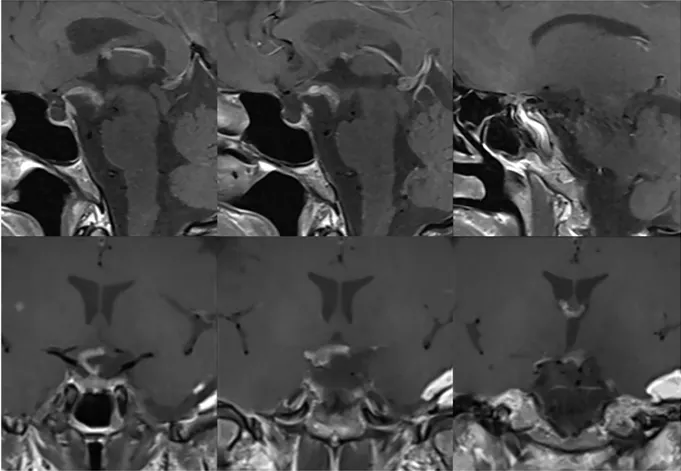

具体分析:MRI显示一个球形病变占据垂体漏斗后部及鞍上间隙,且肿瘤与垂体柄和正常垂体组织紧密相邻(黄色箭头)。

视交叉(绿色箭头)和动眼神经(蓝色箭头)由于受到肿瘤挤压而产生移位,视交叉已经变薄。此外,肿瘤与颈动脉(白色星号)、后交通动脉(红色箭头)、大脑前动脉(白色星号)和大脑后动脉(黄色箭头)紧密粘连,术中剥离困难,存在较大的出血风险。

要求:手术必须要在保留垂体及其功能的基础上进行安全切除,同时不损伤周围重要神经血管,谨慎将肿瘤与其剥离开来。

“为了病人而战!”在福教授的手术理念下,这场与垂体细胞瘤的艰难战役正式开启。在福教授的精细操作下,肿瘤慢慢与周围结构分离,同时,为了保留内分泌功能,福教授并未完全切除肿瘤,而是为了保留关键结构,有意沿着垂体柄和视交叉留下了薄薄的残留物,而这也将为安娜醒来后的生活质量打下稳固的基础。

由于进行了术前栓塞,术中并未出现任何出血及并发症,最终这个棘手的肿瘤被成功切除。安娜的预后良好,并在短短一周后出院,期间没有出现新的神经或内分泌功能障碍。组织病理学证实了垂体细胞瘤的诊断。